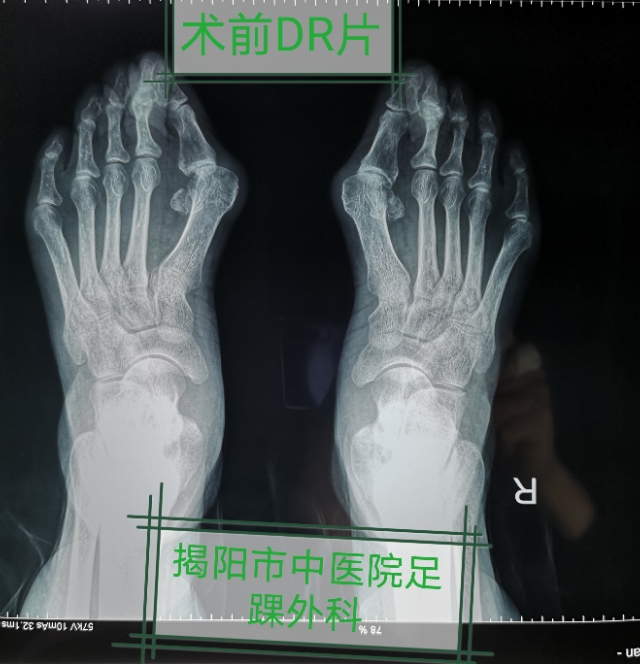

黄老师几十年来一直承受着足部疾病带来的困扰,大踇趾反复红肿疼痛,无法穿鞋行走,了解到揭阳市中医院足踝外科(粤东首个也是唯一一个足踝专科)可能能治疗,前来就诊。原来黄老师从小就有踇趾外翻,无奈不知道那里能治疗,经过详细诊查后林旭裕主治医师为黄老师制定了无痛微创踇外翻矫形手术治疗个性化方案,解决了困扰她几十年的足部顽疾。

林旭裕主治医师科普:踇外翻,俗称“大脚骨”病,简单说就是大脚趾根部的骨头,向内侧“跑偏了”,从外观看,像是多长出来了一块骨头。除了影响美观之外,更重要的是会引起大脚趾内侧疼痛、红肿,畸形形成后,难以自行矫形,局部疼痛逐渐加重,步行困难,男女比例1:9~1:15。